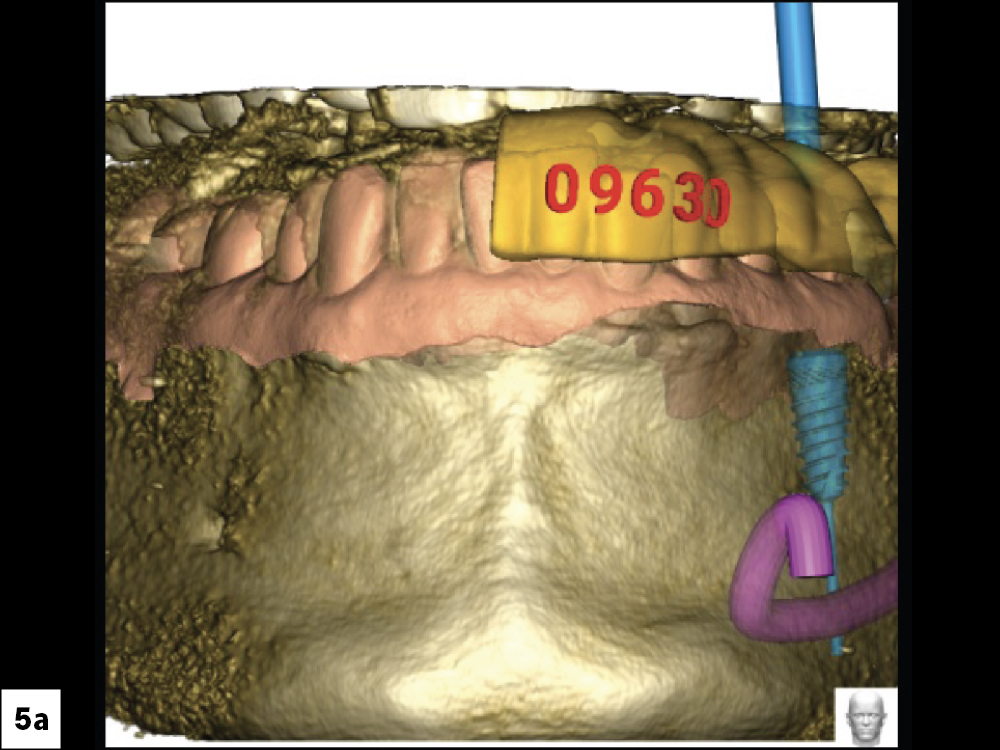

CBCT Scan (Front View)

CBCT Scan (Top View)

CBCT Scan (Left View)

CBCT Scan (Right View)

Figures 5a–5d: Treatment planning was done by Glidewell’s Digital Treatment Planning (DTP) team, which used CBCT scans to determine the ideal position of the implant.